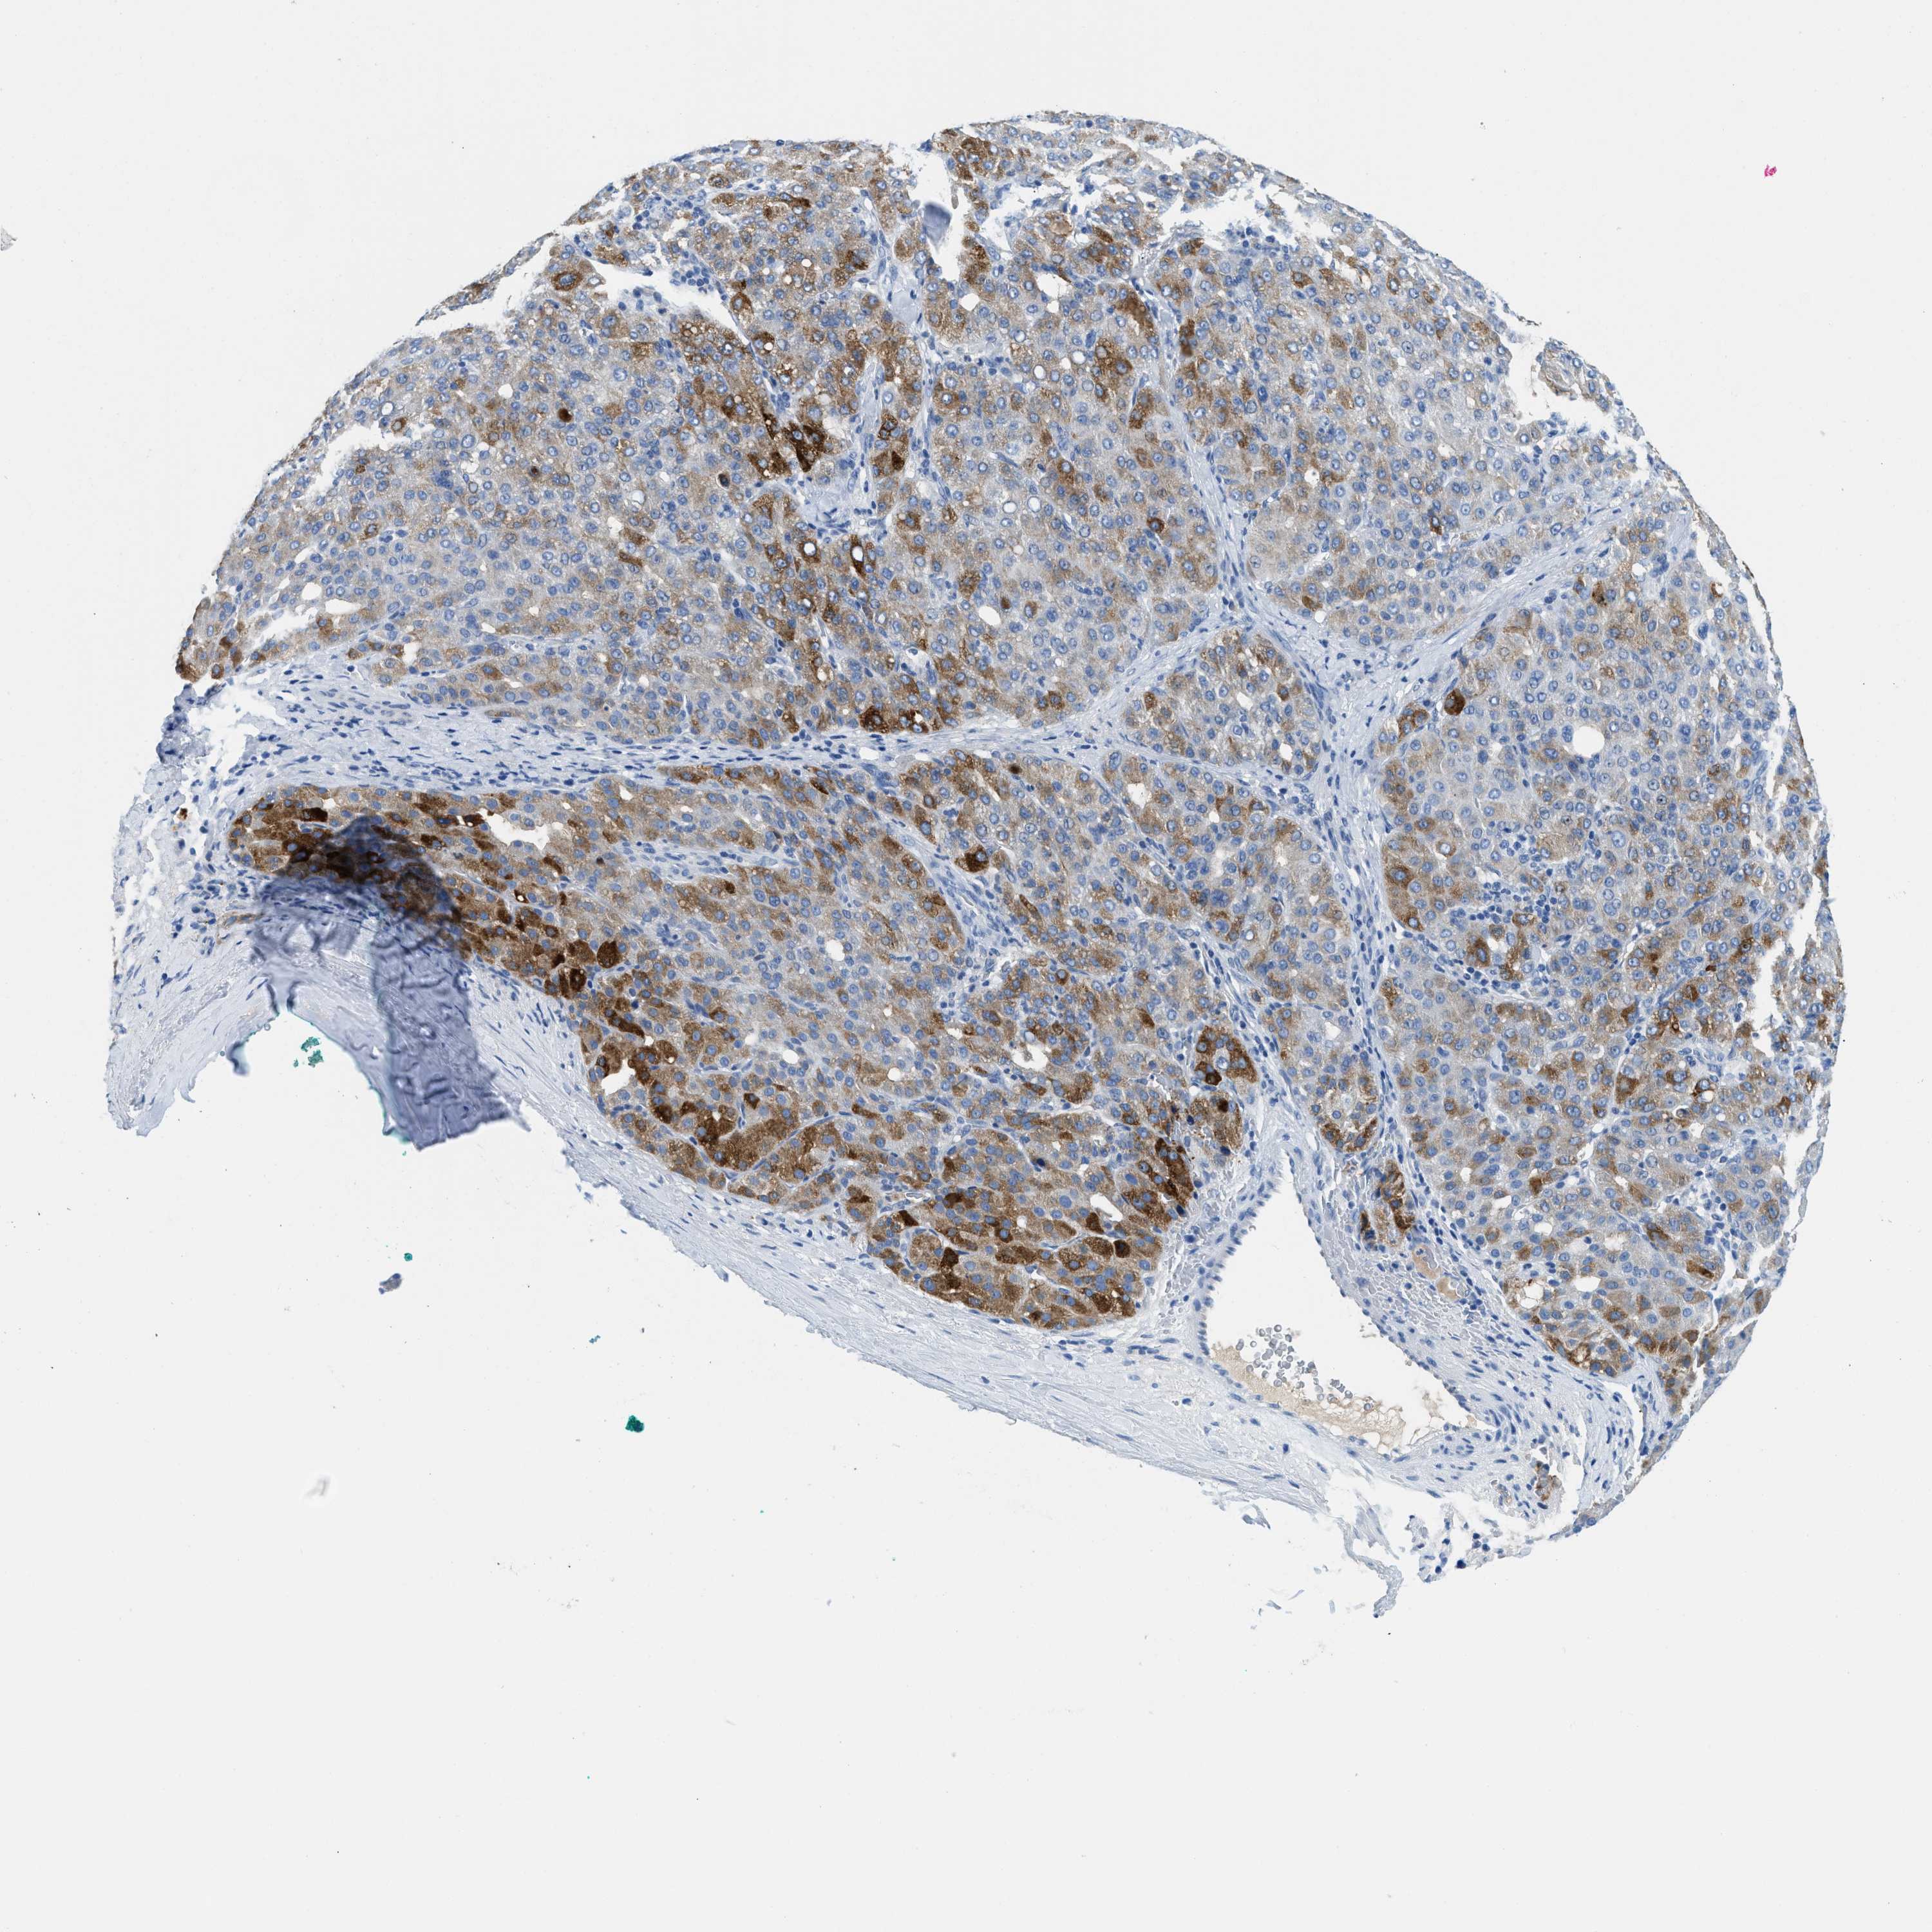

LIVER CANCER - Protein expressioni

A mouse-over function shows sample information and annotation data. Click on an image to view it in a full screen mode. Samples can be filtered based on level of antibody staining by selecting one or several of the following categories: high, medium, low and not detected. The assay and annotation is described here.

Antibody stainingi

Antibody staining in the annotated cell types in the current human tissue is reported as not detected, low, medium, or high, based on conventional immunohistochemistry profiling in selected tissues. This score is based on the combination of the staining intensity and fraction of stained cells.

Each image is clickable and will lead to virtual microscopy that enables deeper exploration of all samples and also displays staining intensity scores, fraction scores and subcellular localization as well as patient and tissue information for each sample.

Antibody HPA002027

Antibody CAB016782

Staining

High

Medium

Low

Not detected

Intensity

Strong

Moderate

Weak

Negative

Quantity

>75%

75%-25%

<25%

None

Location

Nuclear

Cytoplasmic/membranous

Cytoplasmic/membranous,nuclear

Carcinoma, Hepatocellular, NOS

Cholangiocarcinoma